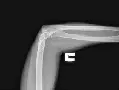

Інформативність обстеження: На рентгенограмах визначаються дистальний відділ плечової кістки і проксимальні відділи кісток передпліччя, ліктьовий і вінцевий відростки ліктьової кістки, головка і шийка променевої кістки, ліктьового відростка і заднього відділу суглобової поверхні блоку плечової кістки, ліктьовий відросток ліктьової кістки, медіальний і латеральний надвиростки плечовий кістки, головка променевої кістки, рентгенівська суглобова щілина плечелоктевом суглоба.

Обстеження призначене для вивчення рентгенівської суглобової щілини, структури і контурів суміжних решт плечової кістки і кісток передпліччя, обстеження в бічній проекції є обов’язковим при дослідженні ліктьового суглоба, так як тільки при рентгенографії в двох взаємно перпендикулярних проекціях можуть бути правильно оцінені зміни і в самому суглобі, і в суміжних відділах кісток.